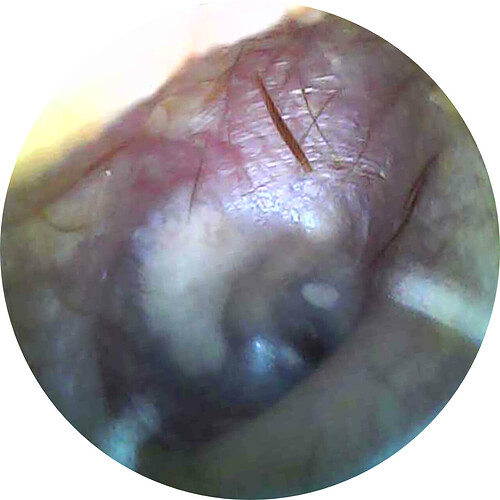

- Now onto this year, I finally got better back to full health in late November early December 2024 and sadly started to get another sinus infect in January and still no answers to why. I just happen to be watching YouTube when a Dentist had said that your teeth could be linked to sinus issues causing sinus infections and normally the only way to tell if this is the case is to get a Cone Beam CT scan. I then thought this could be another lead to find out why I keep getting sick as I did when I was 10 have my first top premolar on my left side removed against what I wanted as they said my teeth were too crowded and it needed to be removed so I could have braces (which that dentist didn’t even do my braces anyway). But I thought when he removed it if a small piece of the root was still in there as he just broke out the tooth without removing it via surgical means that that could cause an abscess in my Left Maxillary Sinus where infections always start. So, finally I was able to find a place that would give me a Cone Beam CT scan back in February of this year all while I was just starting to get sick from my infection. Anyway, I finally got the report in March and found out oddly my Left side is mostly normal other than mucus polyps, but I have a few other issues (I have attached the report below). This report is where I first found out about Eagle Syndrome as it states I might have Calcified Ligaments and further testing is needed to confirm. It was only after this report and looking up what Eagle Syndrome was that I can say I have almost every symptom that has ever been reported. Sadly, I couldn’t find anyone in my State at the time that work with Eagle Syndrome and when I did was about a week before I found this site and the doctor I did see seemed to dismiss me as another hypochondriac and you can’t have it as you don’t have Vertigo type Dizziness, my styloid are normal length and I don’t have neck pain equivalent to having to be in a neck brace. Not only this she only looked at my CT scan from a week earlier that I had got in Emergency. The Emergency visit was due to the fact at 8PM that night I had pain in my Right Mastoid Bone, and I was starting to get an earache. I went to lay down and took pain meds and an ice pack in hopes to reduce the pain and swelling. I couldn’t sleep due to the pain and came upfront about 10PM. 10:21PM I couldn’t take it anymore and started to stretch my neck and I felt a huge snap and heard a load pop, all the pain just felt like it disappeared. One minute later, I had a massive pain that spread just like when you get an IV that stings, but it felt like someone was trying to murder me and stabbed a knife into the right side of my skull. I was in so much pain that I was hunched over, and we had to have an ambulance called. I thought I was having an aneurism and my mother thought I was having a Stroke (very rare ES Symptom). When the ambulance arrived, they took my vitals, and my blood pressure was 148/110 with a pulse in the high 90’s low 100’s. Luckily the pain had subsided enough that we were able to go to emergency without the ambulance ride, but while I was in emergency the pain had spread to my left side of my head and now felt like someone had taken a clothes iron and stuck it on my head. Any breeze moving my hair was pure agony and I couldn’t lay my head on a pillow without that burning pain. According to emergency though I must have just had a Mastoid Process infection and it burst. Luckily the pain went away by the time I went to the Doctor for ES, but like I said before they were of no help.

- Ear Pain (Mostly only during a really bad sinus Infection)

- Pulsating Tinnitus (Last year while just getting out of a doctor’s appointment for my father and his health problems, we had stopped to get gas for the trip home. Right after we got gas my right eardrum was pulsating with my heart and caused extreme Vertigo; one of the very few times I’ve gotten it. It went away after 5 minutes but came back again about 5 minutes later for another 5 minutes. This is the only time I’ve had my eardrum pulse tinnitus; I do hear my pulse about once a month when I sleep though and have my ear on my pillow, but I don’t think that’s true tinnitus.)